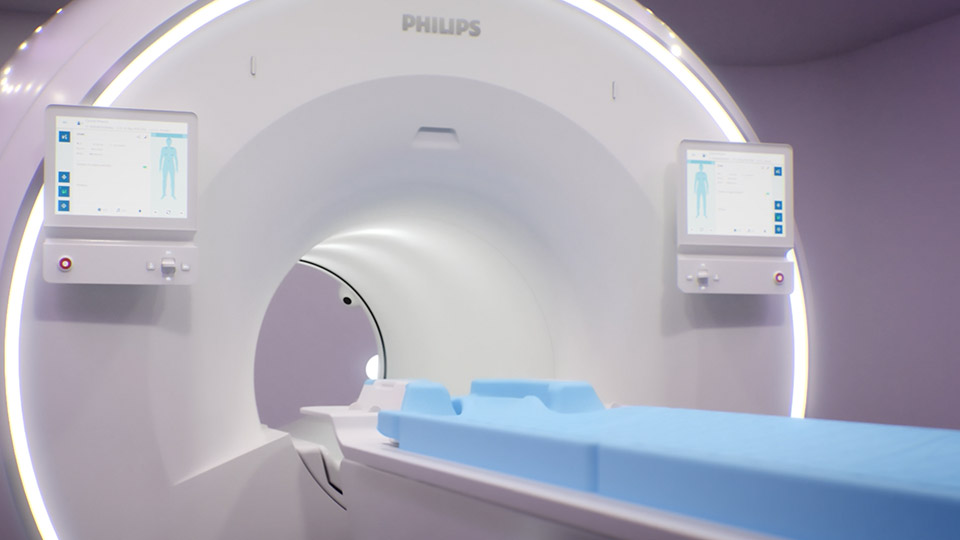

A revolutionary breakthrough in diagnosic quality and speed

Ingenia Elition 3.0T X

A revolutionary breakthrough in diagnostic quality – and speed

Ingenia Elition 3.0T S

3.0T imaging at your fingertips